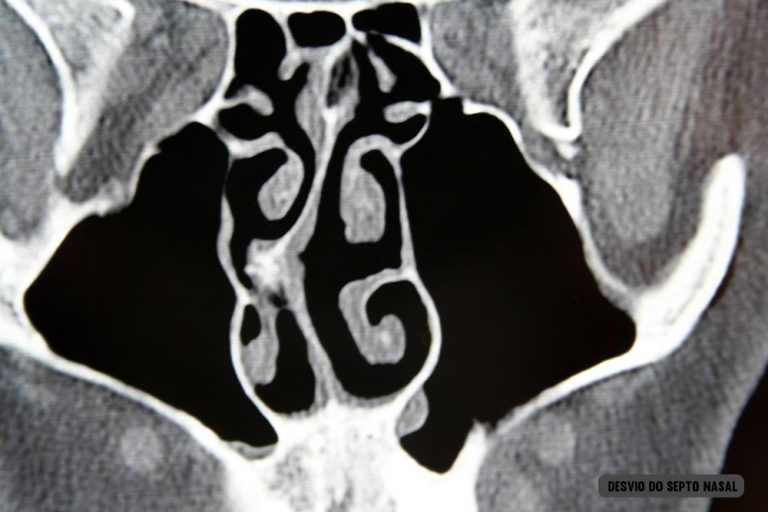

Desvio do septo nasal: tratado com septoplastia ou ressecção do septo. Muito frequentemente realizada junto com a rinoplastia.